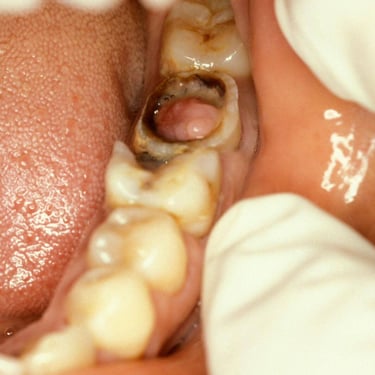

Pulpitis Crónica Hiperplásica

La pulpitis crónica hiperplásica es una inflamación de la pulpa con crecimiento excesivo de tejido pulpar a través de una caries abierta.

Los pacientes notan un tejido rojo que sobresale de la cavidad dental.

El tratamiento incluye la eliminación del tejido afectado y un tratamiento de conducto. Es crucial tratar la caries para evitar infecciones adicionales.